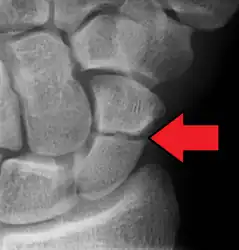

An X-ray showing a fracture through the waist of the scaphoid